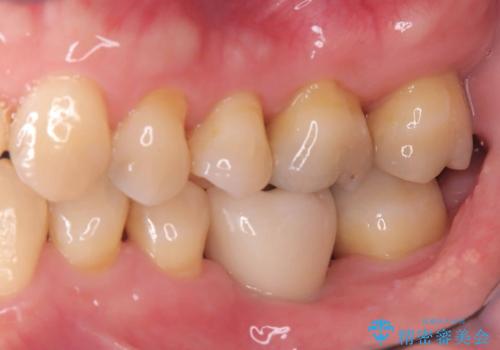

インプラント治療は手術が一度で完了し、術後の痛みもほとんどありませんでした。

機能面・審美面ともに大きく改善され、患者様にも大変ご満足いただけました。